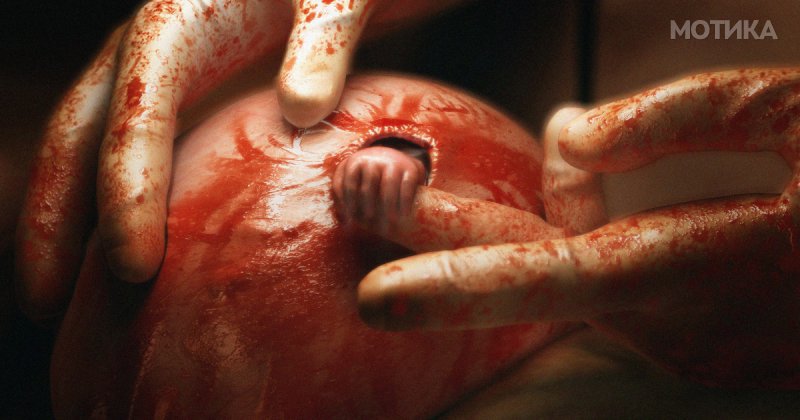

Крајно ризичната операција била спроведена успешно… и одеднаш на крајот на операцијата, преку отворот на мајчината утроба, малата рака го стегнала прстот на хитутгот како да сака да му искаже благодарност!

Токму оваа трогателна и неочекувана сцена фотографот успеа да ја фати и така сликата со наслов “Рака на надежта” стана позната во целиот свет.